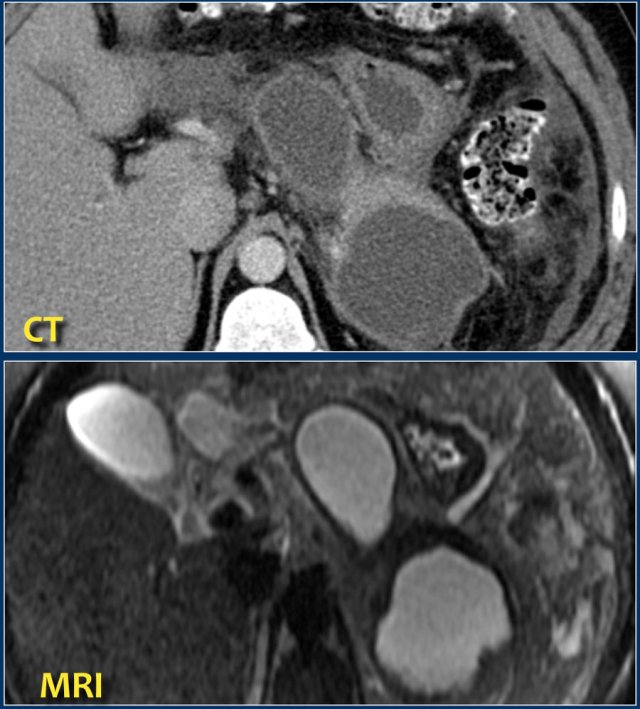

MRI

MRI is superior to CT in differentiating between fluid and solid necrotic debris.

Here a patient with several homogeneous peripancreatic collections on CT.

These collections also show homogeneous high signal intensity on a fat-suppressed T2-weighted MRI image, are fully encapsulated and contain clear fluid (i.e. pseudocysts).

This patient had an acute necrotizing pancreatitis with onset 2 months earlier.

The CT-image shows a homogeneous peripancreatic collection in the transverse mesocolon (arrow).

A T2-weighted MRI sequence shows that the collection has a low signal intensity (arrow).

Most likely this is necrotic fat tissue (i.e. sterile necrosis or walled-off necrosis).

This patient had no fever or signs of sepsis.

Endoscopic or percutaneous drainage would have little or no effect on its size, but increases the risk of infection.